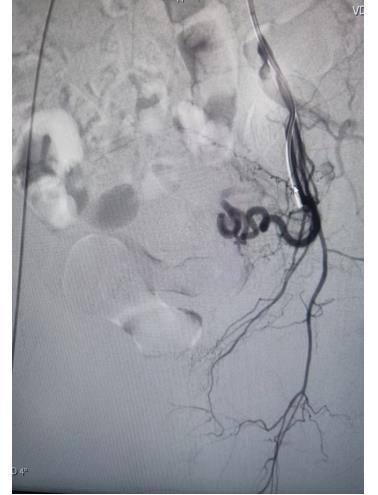

子宮動(dòng)脈栓塞術(shù)屬于血管介入性治療,方法是于股動(dòng)脈穿刺進(jìn)針插入導(dǎo)管,在X射線造影下定位進(jìn)入兩側(cè)子宮動(dòng)脈,注入栓塞劑完全栓塞子宮動(dòng)脈,從而達(dá)到止血或讓子宮肌瘤和病灶缺血壞死的目的;2022年12月6日,在崔旭輝主任、孟慶槐副主任醫(yī)師、馬力主治醫(yī)師等我院介入團(tuán)隊(duì)協(xié)作下,成功為患者進(jìn)行了雙側(cè)子宮動(dòng)脈栓塞術(shù),術(shù)后患者子宮異常出血停止,效果立竿見影,患者病情恢復(fù)良好。

右側(cè)子宮動(dòng)脈栓塞前后對(duì)照